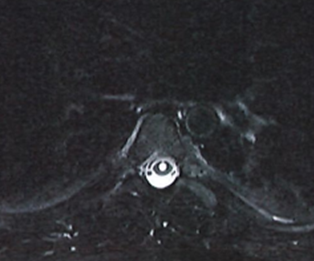

Fig 2. MRI of thoracic spine showing syringomyelia.